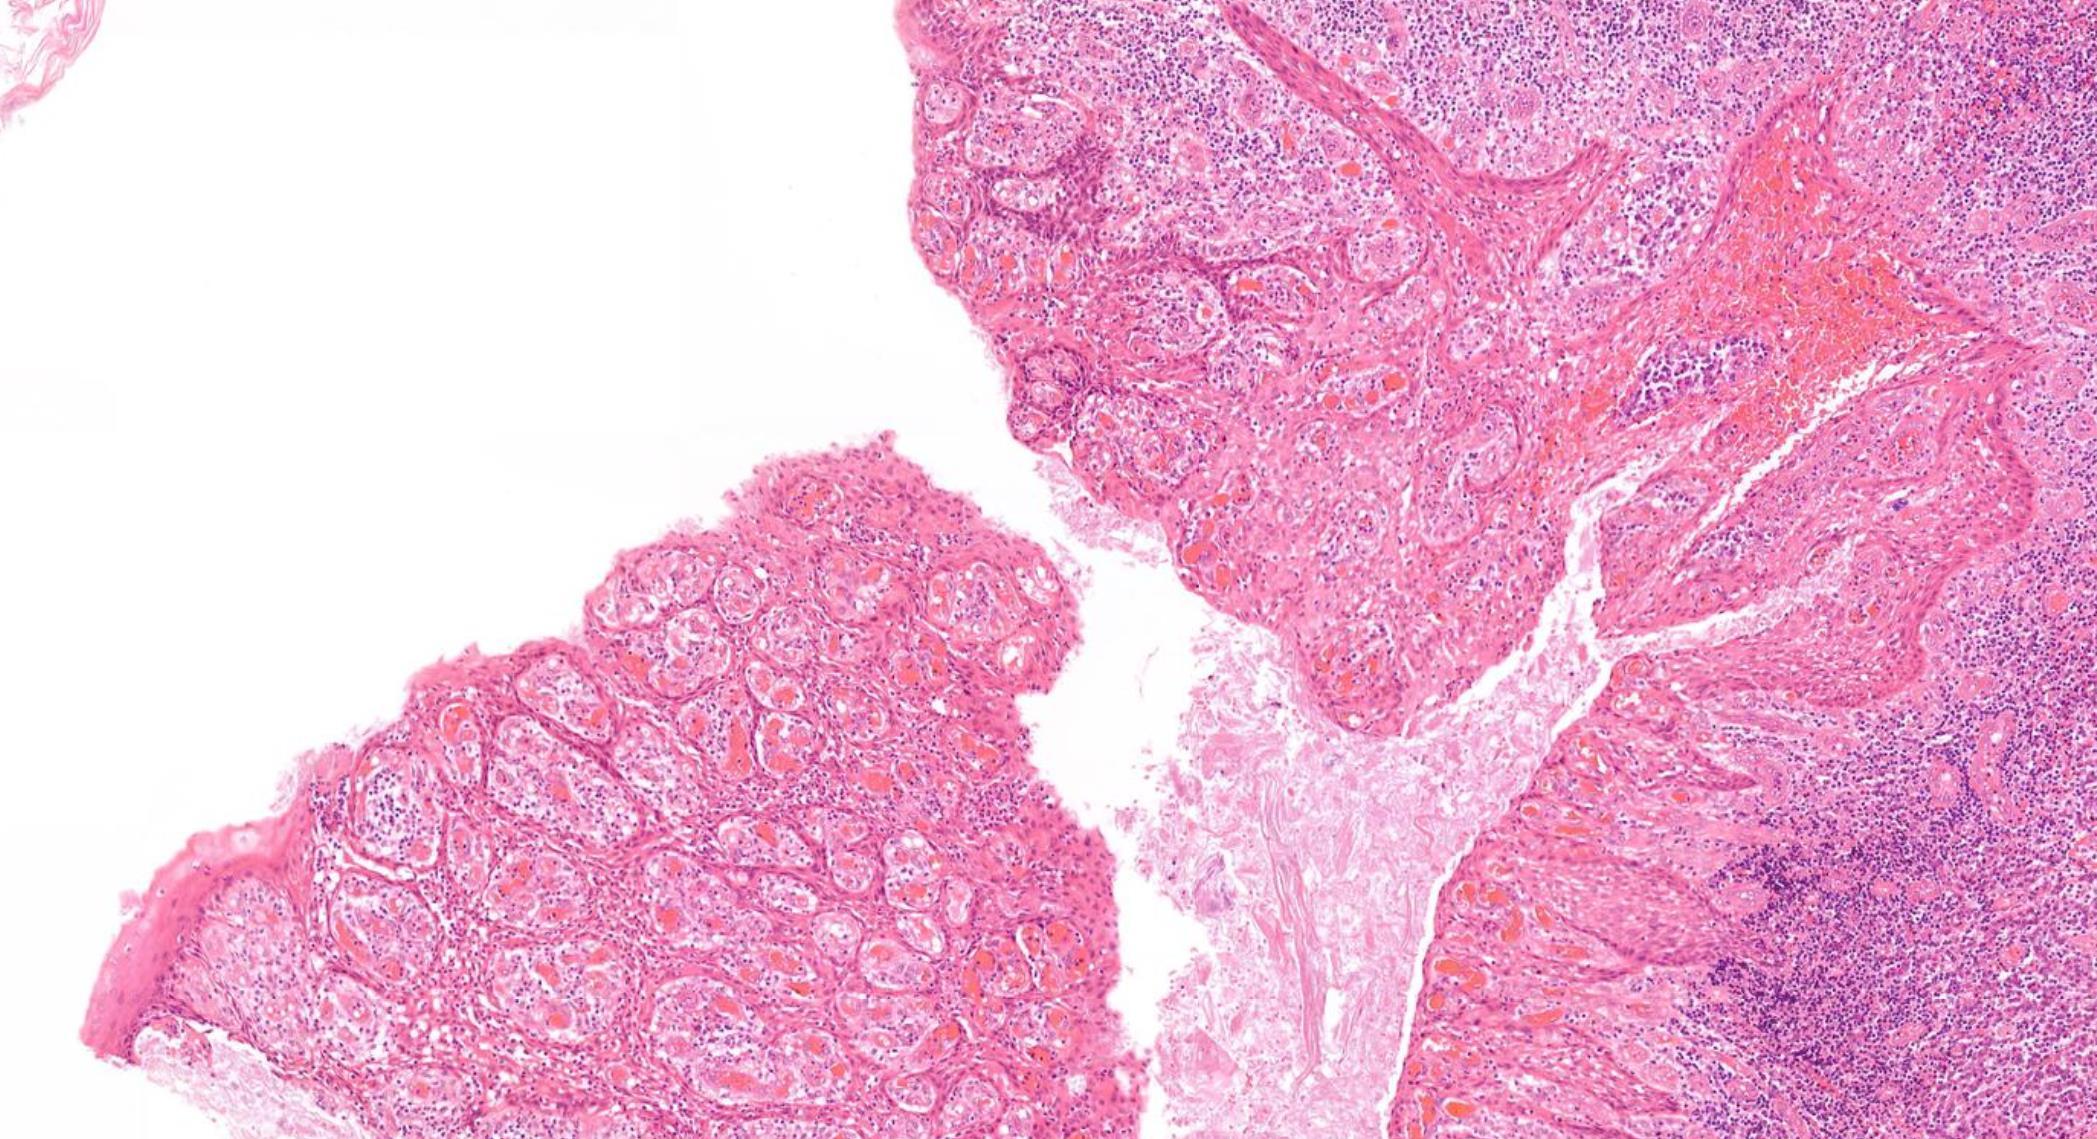

More common in young adults

Foci of abrupt keratinization

Pancytokeratin+, p63+, p40+, NUT1+ t(15;19); BRD4-NUT gene fusion

NUT midline carcinoma